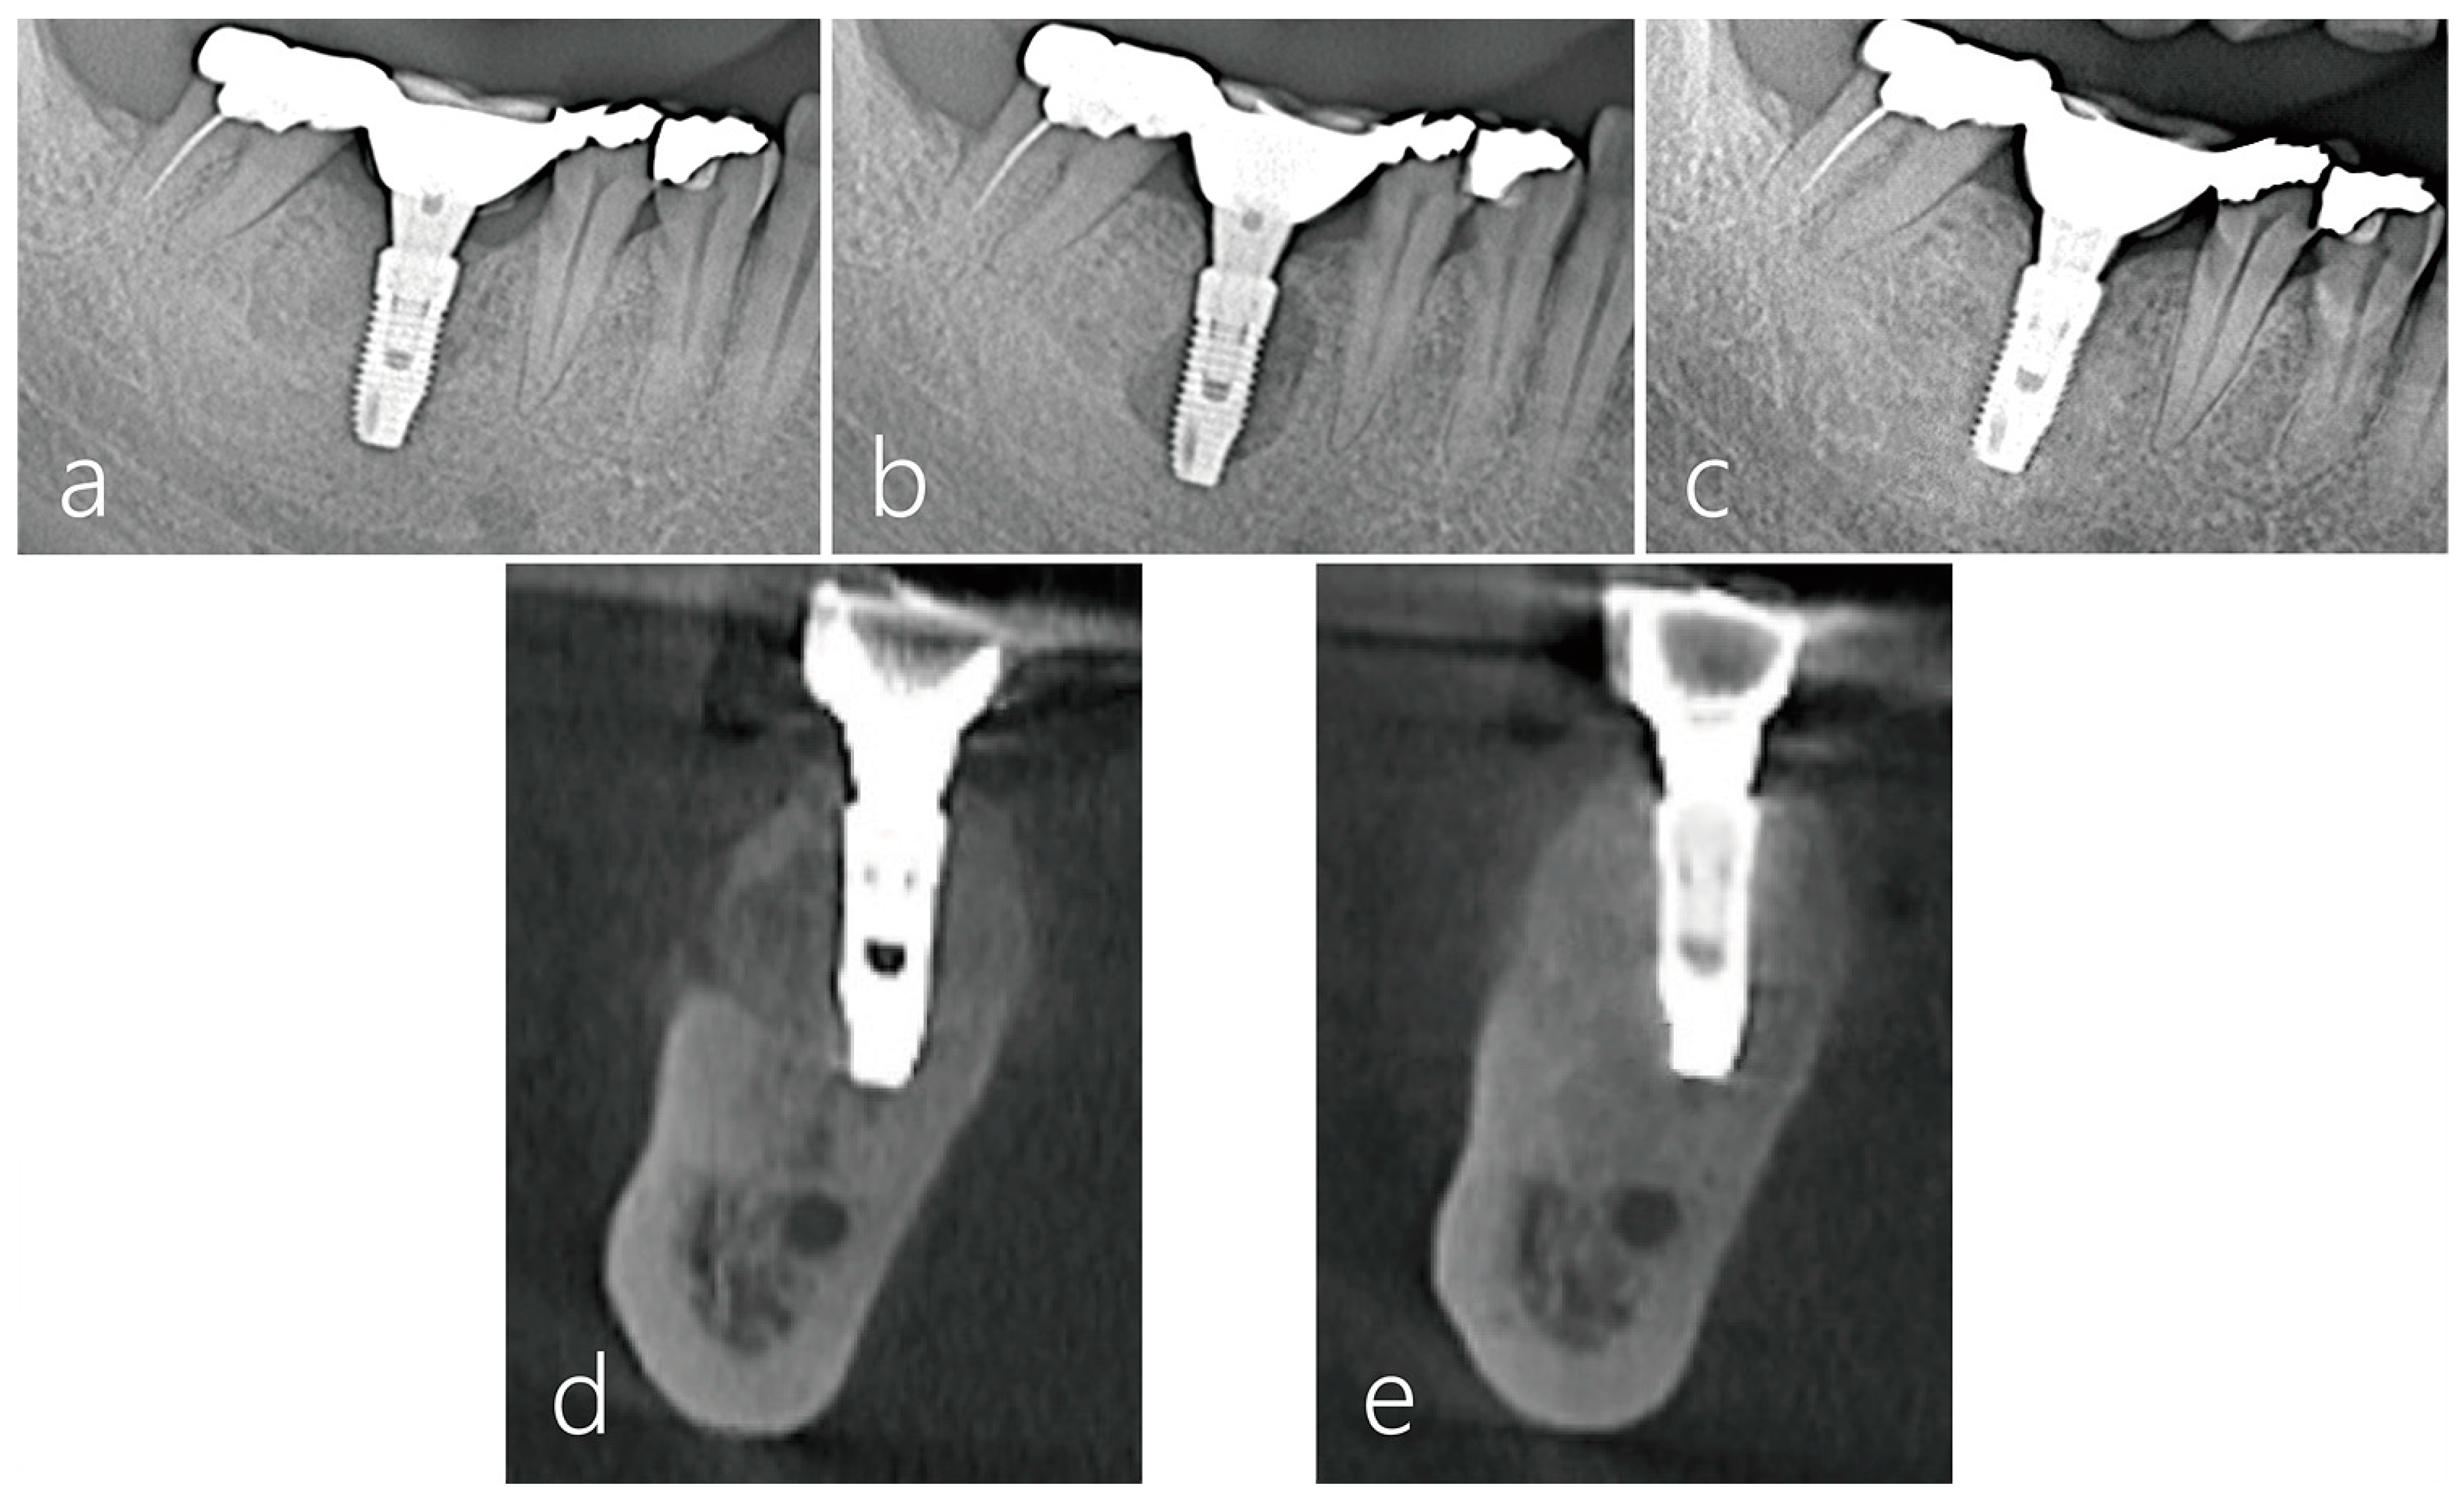

2.4. Surgical Reentry

2.6. Radiographic Evaluation